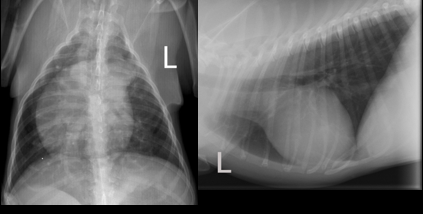

• Quality is good. Little axial rotation (some curvature in DV). Lateral has some rotation. Both inspiration.

• Underexposed (white). (note: overexposure is like toast and it goes black!)

• Vertebral heart score of 10 (high end of normal)

• Right sided heart enlargement

• Expiratory film

• Bulging PA (LAA would be more 3 o clock in DV)

• Cardiac silohouette

–Big

–Left is rounded and normal

–R: marked enlargement and towards wall

• Weird things cranial to heart ventral edge of mediastinum (due to PA enlargement)

• Apex to trachea bifurcation – 3-4:1

• Cranial lobar vessels – small! O this might be why we see so many lung markings

• No pleural disease